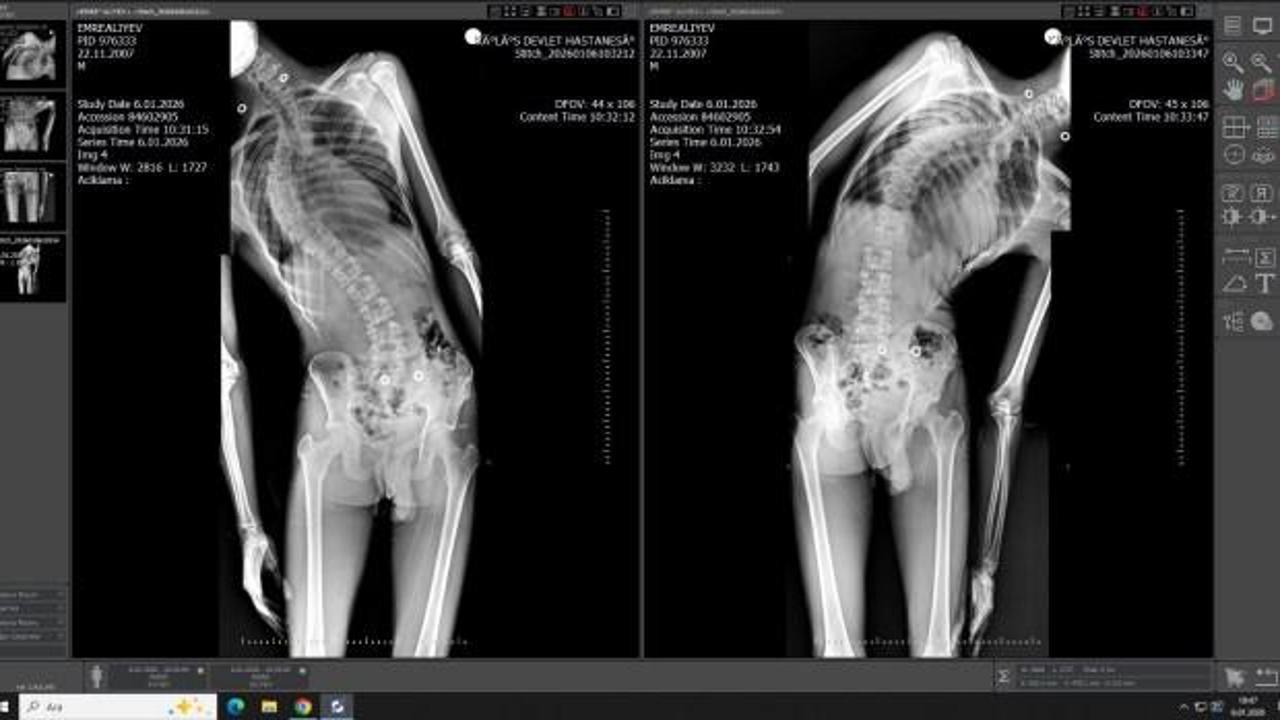

Mersin’in çarşı merkezinde hizmet veren tek devlet hastanesi olan Toros Devlet Hastanesi, sağlık alanında önemli bir başarıya daha imza attı. Kilis’te yaşayan ve ileri derece omurga eğriliği (skolyoz), kamburlaşma ile solunum sıkıntısı yaşayan 18 yaşındaki hasta, birçok merkezde gerçekleştirilemeyen zorlu ameliyat sayesinde sağlığına kavuştu.

Yapılan muayene ve ileri tetkikler sonucunda hastaya ileri derecede skolyoz tanısı konuldu. Yaklaşık dört yıldır fizik tedavi gören hastada, omurga eğriliğinin ilerlemesi durdurulamayınca solunum problemleri de ciddi boyutlara ulaştı. Bunun üzerine cerrahi müdahale kararı alındı.

İl dışından hastanemize başvuran hastamızın skolyozu yaklaşık dört yıl önce tespit edilmişti. Bu süre boyunca düzenli fizik tedavi görmesine rağmen eğrilik ilerlemiş ve ciddi solunum problemleri ortaya çıkmıştı. Yaklaşık 10 saat süren başarılı cerrahi müdahale ile omurga eğriliği düzeltildi.

Ameliyat sonrası hastamızın boyu yaklaşık 4 santimetre uzadı, solunum fonksiyonlarında belirgin düzelme sağlandı. Hastamız, ameliyattan 10 gün sonra şifa ile taburcu edildi.